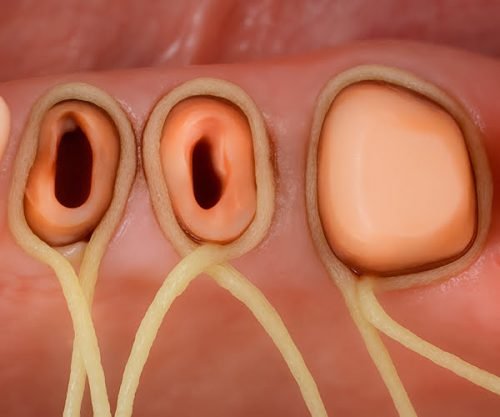

Achieve rapid tissue displacement, precise margins and high quality impressions. Retrax® Cord is the foundation for success in both conventional and digital dentistry. The entire Retrax cord line is ideal for creating full exposure of the margin.

Tissue Management and Clear Margin Exposure are Key in Both Analog and Digital Dentistry

Tissue Management and clear exposure of the margin, is the foundation of all Analog and Digital Dentistry